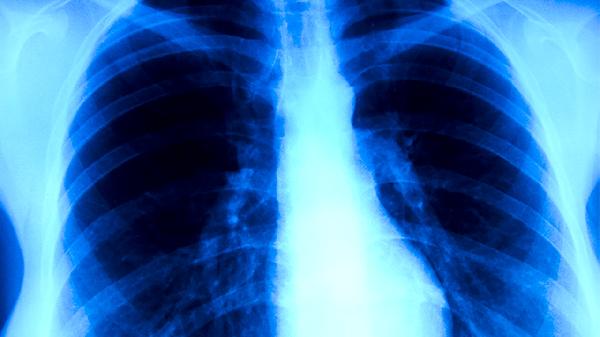

支气管肺炎康复阶段常见表现有哪些

支气管肺炎进入恢复阶段后,主要表现包括咳嗽减少、痰量变少、体温稳定、呼吸变得顺畅以及食欲逐渐恢复。这些改善通常是因为炎症减轻、组织开始修复、免疫系统恢复正常、气道清理功能增强以及肺部功能逐步恢复。